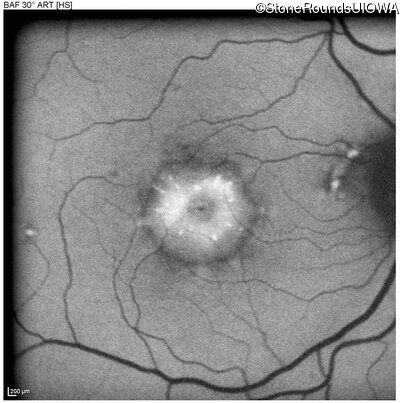

Blue Autofluorescence - Right - 20/40 -1

Exemplar